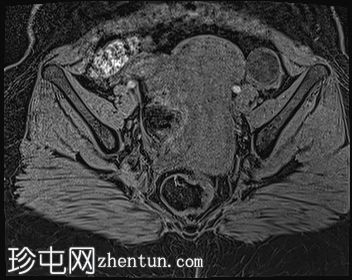

轴位

T2加权像

3.jpg

子宫体积增大,宫底可见息肉样病变,T2加权像呈异常中高信号强度。病变可见轻度扩散受限,增强后呈均匀强化。病变与宫底交界区之间可见一界限清晰的异常高T2信号区域,可能为囊性变性。未见病变超出交界区。

在剖宫产切口远端的前壁上,可见另一处类似的较小病灶。

左侧附件囊性病变,T1加权像信号异常低,T2加权像信号异常高。无增强扫描强化。

子宫内膜息肉是子宫内膜组织的结节状突起。通常表现为T2加权像信号异常高,增强扫描后呈均匀强化。

病理检查通常显示增生期子宫内膜紊乱。